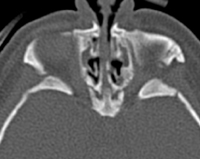

Vol. 109, No. 5 / NASAL PYRIFORM APERTURE STENOSIS FIG. 1. Computed axial tomographic image taken at the level of the lower nasal cavity, demonstrating focal stenosis of ... Read More